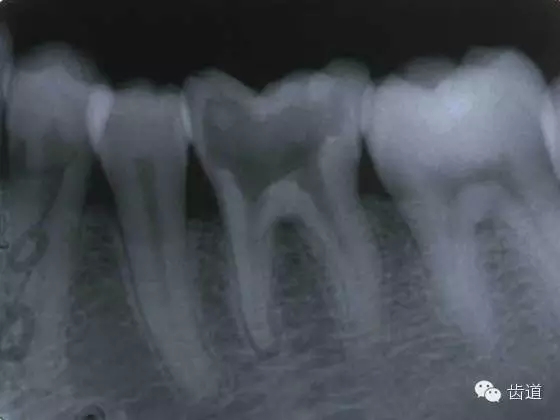

原因:根管堵塞,肩臺(tái)形成,器械折斷,根尖區(qū)牙本質(zhì)碎屑堆積等。

預(yù)防原則:參考點(diǎn)固定;止動(dòng)片位置固定;預(yù)彎所有根管銼;注意根管銼的彎曲應(yīng)與根管彎曲一致;X線投照角度要一致;保持根管的原形預(yù)備;反復(fù)用小號(hào)的銼通暢根管逐號(hào)預(yù)備根管。

原因:牙本質(zhì)碎屑,充填材料堵塞根尖區(qū)等。

預(yù)防原則:開(kāi)髓之前去凈齲壞組織和無(wú)基釉等,根管口預(yù)備要充分;大的充填體,全冠開(kāi)髓時(shí)要噴水,大量沖洗可去除碎屑,根管銼再次進(jìn)入根管應(yīng)清潔;根管銼不可跳號(hào);反復(fù)使用小號(hào)的銼通暢根管,根管銼不可過(guò)度旋轉(zhuǎn)或用力;勿在干燥情況下預(yù)備根管;暫封完善。

處理方法:試用15#K銼或擴(kuò)大器通過(guò)堵塞處,10#K銼尖端3-4mm彎成45度角,沿堵塞物周緣旋轉(zhuǎn)進(jìn)入,尋找卡住的感覺(jué),一旦卡住,采用向根尖部旋轉(zhuǎn)和小量提拉的動(dòng)作,通過(guò)堵塞部。并照X線確定。EDTA 有幫助。

如果堵塞部不能通過(guò),應(yīng)預(yù)備到堵塞部位,并做根充,定期觀察;也可塑化根尖部,塑化加根充。必要時(shí)根尖手術(shù)。